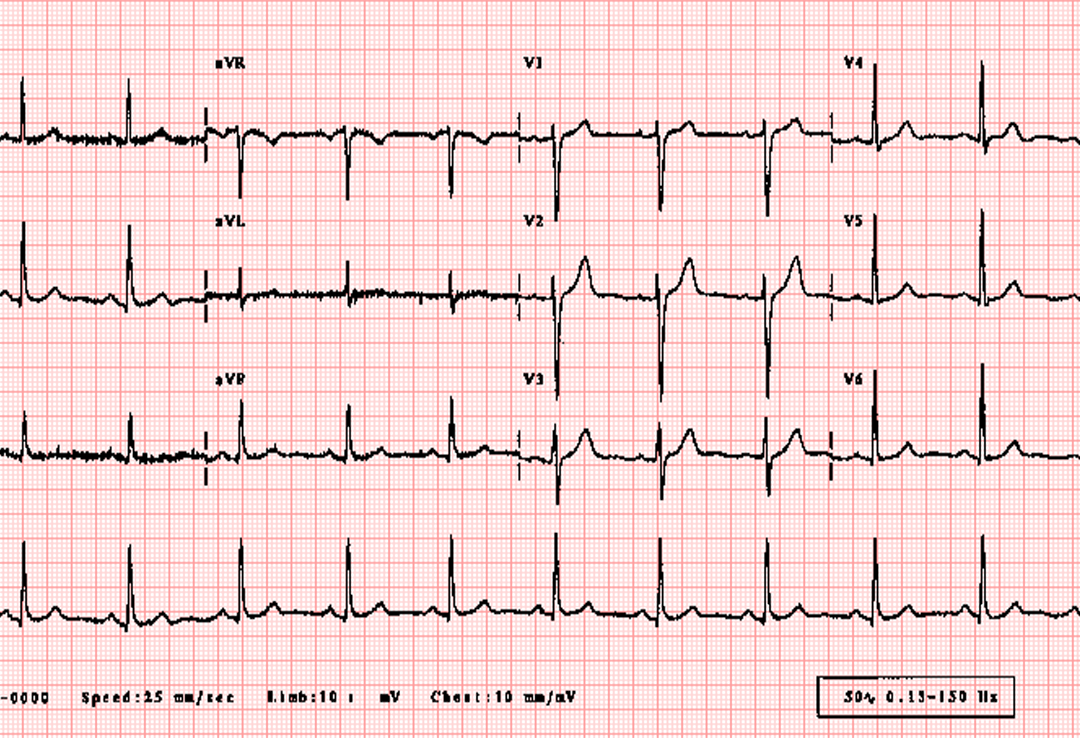

ECG

This division of ours specializes in providing anesthesia care, pain management, and critical care medicine.